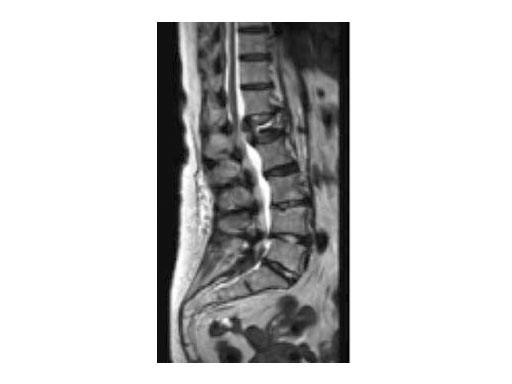

A 78-year-old woman was affected by steroid induced osteoporosis. She had persisting pain (mechanic and muscular) due to static imbalance (hyperkyphosis) and nonunion 8 months after a minor trauma with a vertebral compression fracture and vertebra plana of L1, and development of symptomatic stenosis of the spinal canal with loss of mobility over time. Pre-existing degenerative lumbar scoliosis was increased by the fracture.